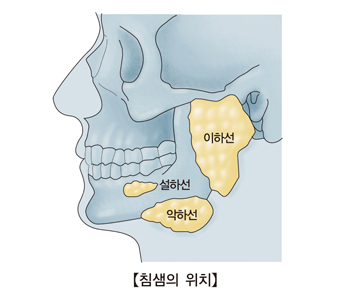

타석증은 침을 생산하는 기관인 침샘(타액선)이나 침샘으로부터 입 안쪽으로 연결된 침샘관, 타액선관에 석회 물질, 이물질, 세균 등이 뭉쳐서 침의 통로를 막아서 발생하는 질환입니다.

타석증의 정확한 원인은 알려지지 않았습니다. 침의 정체, 침샘관의 염증, 손상 등이 원인으로 꼽힙니다. 타석증이 주로 발생하는 부위는 턱밑 침샘인 악하선이 75%로 가장 많습니다. 그 다음은 귀밑 침샘인 이하선에서 약 20% 정도 발생합니다. 그 밖에 다른 침샘에서 5% 정도 발생합니다. 다른 부위보다 턱밑 침샘에서 타석증이 더 많이 발생하는 이유는 이곳이 귀밑 침샘에 비해 침의 정체 정도가 더 심하고 점액 함량이 더 높기 때문입니다.